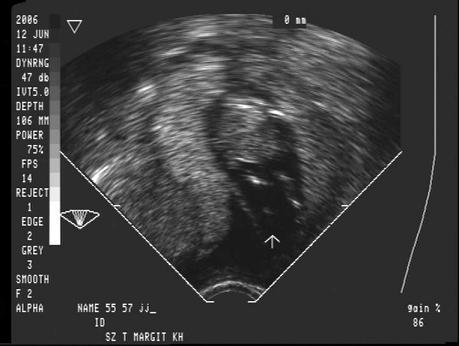

Igen, én is imádom/imádtam a Krizsa dokimat. Nagyon szimpatikus és iszonyú profi. Hormonértékekből simán diagnosztizál. Majd UH és lássatok csodát: igaza volt… Szóval nagyon jó szakember. Bár szerencsére, nekünk nem kellett a végén beavatkozás, de tudom, hogy ő azt is összehozta volna nekünk. Akkor nyugodtam meg (a nődokim után), amikor elmentünk hozzá. Aztán mikor terhes lettem nődokit váltottam